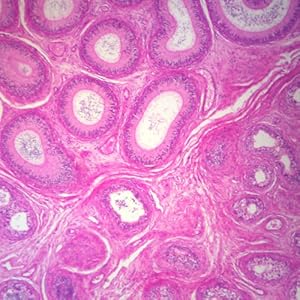

Human Prostate Gland – Young, sec. 7 um, H&E